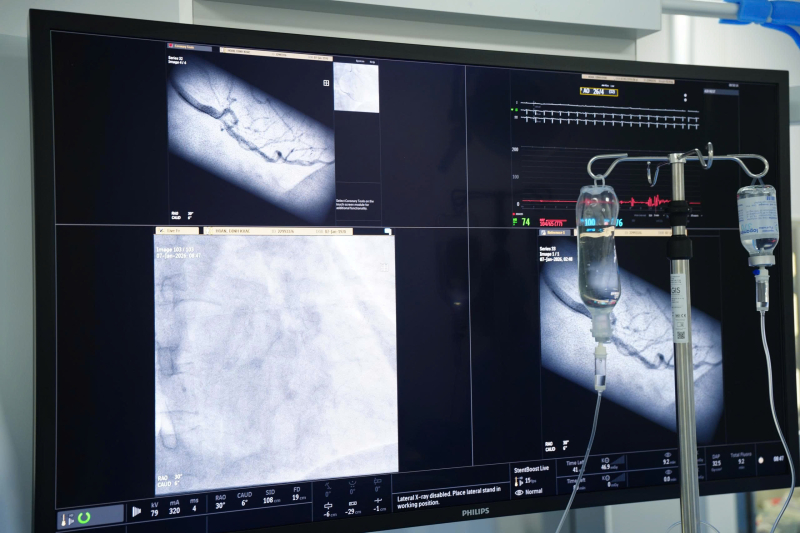

ThS. BS Đinh Danh Trình, Trưởng khoa Tim mạch Bệnh viện Bãi Cháy cùng ê kíp đang tiến hành can thiệp đặt stent cho bệnh nhân trên hệ thống DSA 2 bình diện Azurion thế hệ mới.

Ca can thiệp được tiến hành trên hệ thống DSA 2 bình diện Azurion thế hệ mới. Hình ảnh mạch vành hiển thị rõ nét, trực quan trong suốt quá trình thao tác. Kết quả chụp cho thấy tổn thương hẹp tại động mạch vành phải đã tiến triển, trong khi các stent cũ vẫn thông tốt, không bị tái hẹp. Trên cơ sở đó, các bác sĩ đã quyết định đặt thêm 01 stent mới tại vị trí tổn thương.

Hình ảnh: Động mạch vành phải được tái thông sau khi đặt stent.